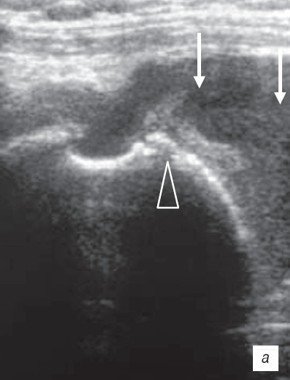

Этот признак также имеет высокую диагностическую значимость. Фокальное истончение в ротаторной манжете следует отличать от истончения сухожилий наружных ротаторов плеча при естественном развитии дегенеративного процесса. Дегенеративно-дистрофические изменения суставов (синдром Милуоки) наиболее часто обнаруживается у пожилых женщин. Это проявляется в виде деструктивной артропатии из-за накопления кристаллов гидроксиапатитного или смешанного фосфата кальция. Клинические признаки совпадают с ультразвуковыми данными, которые выявляют изменения хряща и деструкцию кости, субхондральный склероз, повреждение интраартикуллярных тканей, разрыв ротаторной манжеты и деформацию сустава. Некоторые авторы полагают, что начальные проявления данного заболевания - повреждение ротаторной манжеты плеча, вследствие чего происходит высокое стояние головки плечевой кости и соприкосновение с акромионом и суставным концом лопатки (рис. 3). Такие разрывы могут иногда быть бессимптомными.

а) На сонограмме отсутствует ротаторная манжета, видны гипоэхогенные кровоизлияния (стрелки) и эрозия суставной поверхности головки плеча (коронарный срез плеча) (головка стрелки).